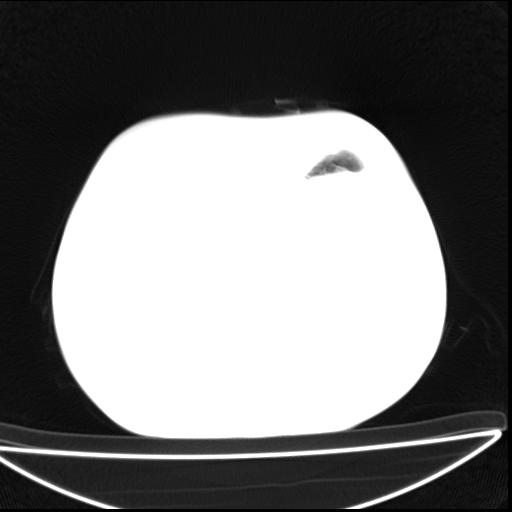

男  70岁,发烧咳嗽4天。盗汗,消瘦。无痰中带血丝,以前有肺tb病史,ct见,双肺tb,左侧胸廓塌陷,左胸膜肥厚粘连。纵隔移位,右侧胸腔积液,大家说说那个心影前左肺舌叶除了肺大炮还有炎症还是干酪性肺炎?有占位吗?我看纵隔淋巴结也大。